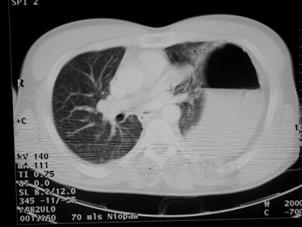

Contuzie pulmonara stanga Contuzie pulmonara dreapta

Contuzie pulmonara dreapta.Imagine CT